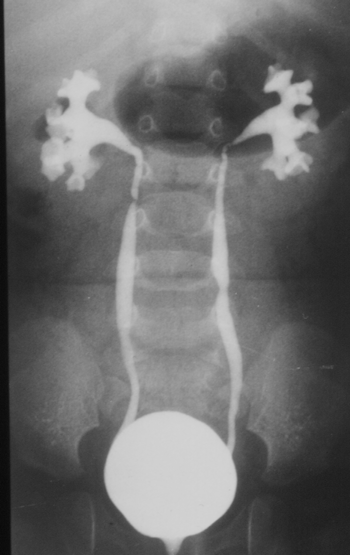

VUR tanısı floroskopi altında yapılan voiding sistoüretrografi veya radionüklid voiding sistografi ile konulabilir. Miksiyon yaptırılmayan, anestezi veya yoğun sedasyon altında yapılan VCU güvenilir değildir. Aşırı hidrasyon, diürez nedeniyle düşük dereceli reflülerin atlanmasına yol açabilir. Şüpheli durumlarda siklik (tekrar edilerek yapılan) VCU ile %12 oranında VUR insidansında artma veya grade değişikliği saptanmıştır (17). Şekil 3, Resim1.

Resim 1 .Voiding

Sistoüretrografi

Şekil 3.VUR

Derecelendirilmesi